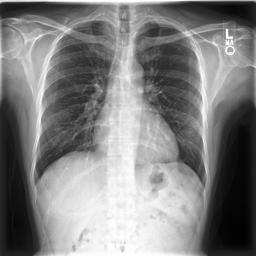

Large numbers of labeled medical images are essential for the accurate detection of anomalies, but manual annotation is labor-intensive and time-consuming. Self-supervised learning (SSL) is a training method to learn data-specific features without manual annotation. Several SSL-based models have been employed in medical image anomaly detection. These SSL methods effectively learn representations in several field-specific images, such as natural and industrial product images. However, owing to the requirement of medical expertise, typical SSL-based models are inefficient in medical image anomaly detection. We present an SSL-based model that enables anatomical structure-based unsupervised anomaly detection (UAD). The model employs the anatomy-aware pasting (AnatPaste) augmentation tool. AnatPaste employs a threshold-based lung segmentation pretext task to create anomalies in normal chest radiographs, which are used for model pretraining. These anomalies are similar to real anomalies and help the model recognize them. We evaluate our model on three opensource chest radiograph datasets. Our model exhibit area under curves (AUC) of 92.1%, 78.7%, and 81.9%, which are the highest among existing UAD models. This is the first SSL model to employ anatomical information as a pretext task. AnatPaste can be applied in various deep learning models and downstream tasks. It can be employed for other modalities by fixing appropriate segmentation. Our code is publicly available at: https://github.com/jun-sato/AnatPaste.

翻译:大量贴有标签的医学图像对于准确检测异常现象至关重要,但人工注解是劳动密集型和耗费时间的。自监学习(SSL)是一种培训方法,用于在不人工注解的情况下学习特定数据特征。一些基于SSL的模型被用于医学图像异常现象的检测。这些SSL方法有效地学习了多个特定领域图像的表解,如自然和工业产品图像。然而,由于医学专业知识的要求,基于SSL的典型模型在医学图像异常现象检测方面效率低下。我们展示了一个基于SSL的模型,可以进行基于解剖结构的、不受监督的异常现象检测(UAAD)。该模型使用解剖-觉粘贴(AnatPaste)增强工具。基于SSL的几种模型用于医学图像异常现象。这些异常现象与真正的异常相似,有助于模型识别这些异常现象。我们在三种开源的胸腔辐射数据集中可以使用模型,在基于解剖面结构结构的曲线下(AUSC),在92.1号中使用解析(Anal-SL)粘度图解为最高格式。